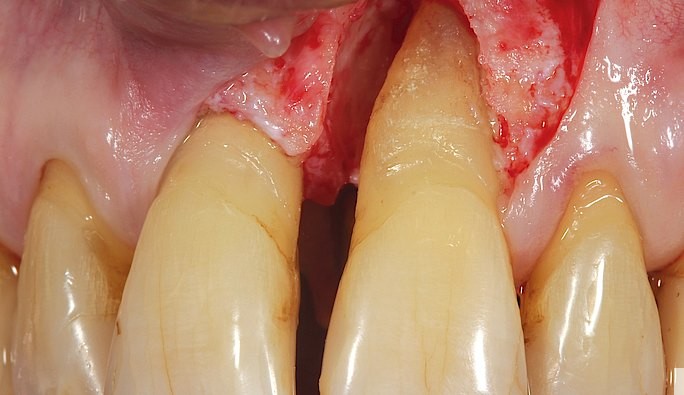

Parodontit iltihabi-degenerativ (dağıdıcı) bir proses olub vaxtında və səmərəli müalicə edilmədikdə dişətrafı sərt və yumuşaq toxumalarda geriyə dönməyən qüsurlara səbəb olur. Bu qüsurlar pasiyent üçün həm estetik həm də funksional çatışmazlıqları özü ilə birlikdə gətirir.

Bu zaman parodontit tam şəkildə müalicə olunsa belə meydana çıxmış bu qüsurlar yalnız bərpaedici cərrahi metodlarla ortadan qaldırıla bilir. Bu zaman pasiyentin öz donor bölgələrindən götürülmüş sərbəst qreftlər, o cümlədən də yumuşaq və sərt toxumaəvəzedici vasitələr, membranlar, həmçinin bərpaedici xassəyə malik proteinlər uğurla tətbiq edilir. Bu prosedurlar defektin növünə, miqyasına, hansı toxumalara siraət etmə xüsusiyyətlərinə görə müvafiq olaraq müvafiq qaydada aparılır.